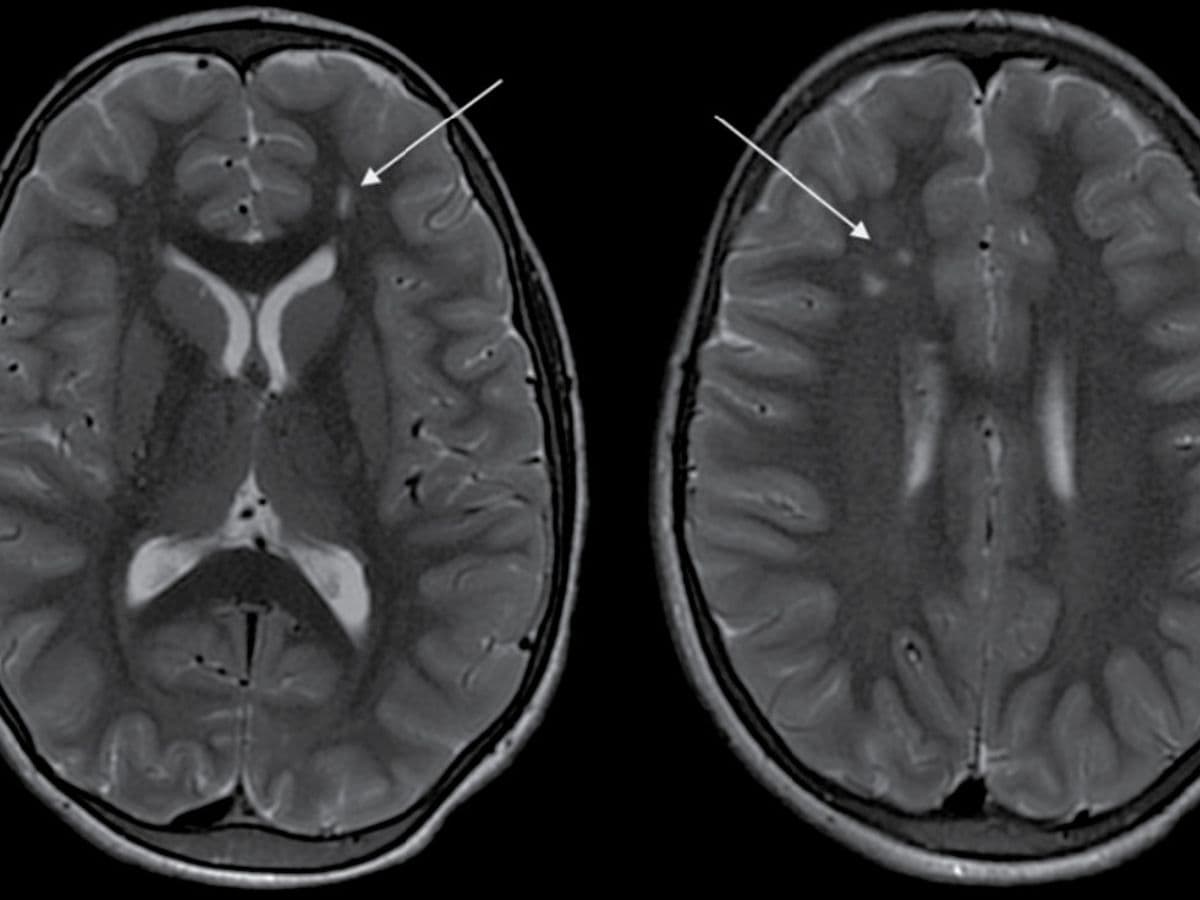

Arjun (name changed) experienced an episode of seizure a year back which was progressively followed by a decline in his ability to see and weakness on the left side of his body over the course of the year. A CT Angiogram at Aster Whitefield Hospital showed a “puff of smoke” appearance - a hallmark sign of Moyamoya disease, hence confirming the diagnosis.

This rare and unique disease mostly affects children around the age of 10 years and adults around the age of 40 years while progressing without warning, necessitating prompt and precise medical intervention. Moyamoya disease causes narrowing of key brain arteries, prompting the brain to form smaller compensatory blood vessels to meet its oxygen needs. These new vessels, however, are often insufficient, appearing as a “puff of smoke” in imaging scans. When the brain’s demand for blood outpaces the supply, patients experience strokes or other neurological events, as in Arjun’s case. Left untreated, Moyamoya can lead to recurring strokes, disability, and even death, making early diagnosis critical to altering the disease's course.